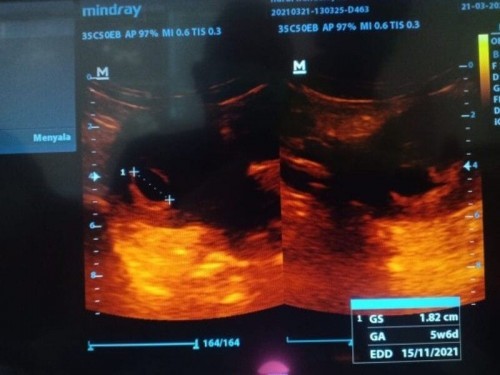

#bantusharing Ternyata selama ini saya hamil kosong 😓 Ya Allah sedih bgt ya Allah 😥😭😭 Ada yg pernah mengalaminya?#seriusnanya #jangandibully #ingintahu

#seriusnanya kalau ga salah umur kemailan saya 9 Minggu , tpi d USG ga kelihatan janin nya ada yg tau ga ya Bun. Trus tdi MLM ada ngefek dikit gitu Bun . Tdi usg hanya kantung janin nya saja. Mohon penjelasan bagi yg tau. Ini foto USG bulan lalu , tdi tidak sempat foto kata dokter masih kelihatan kantung janin nya saja.. 🥺😥 terimakasih